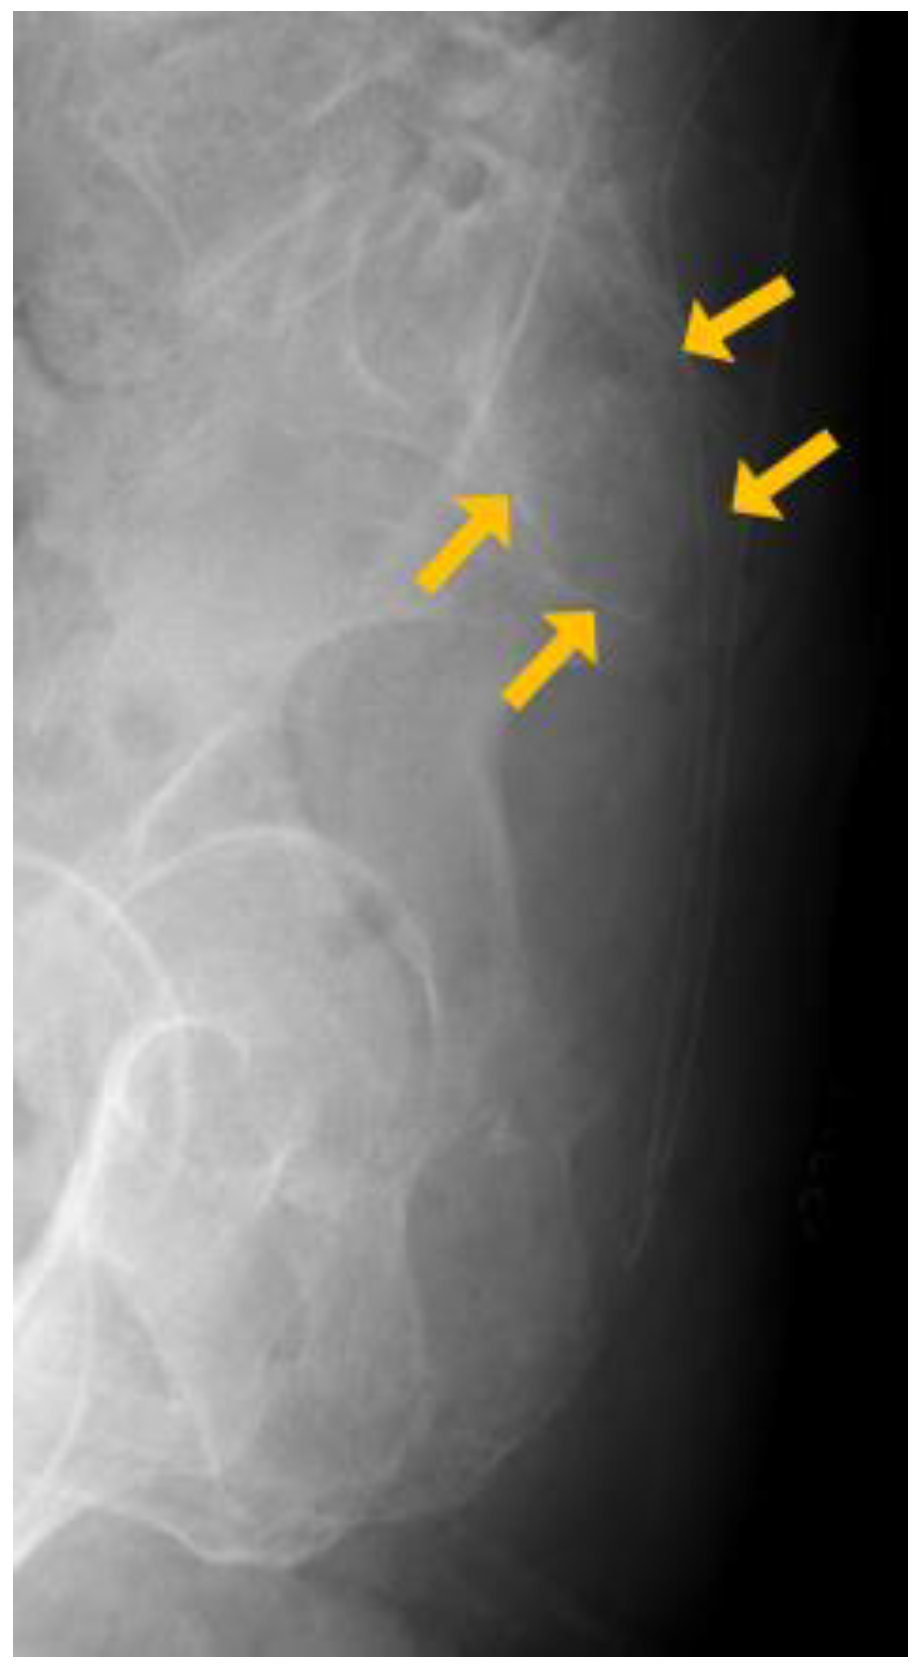

2. Case Report